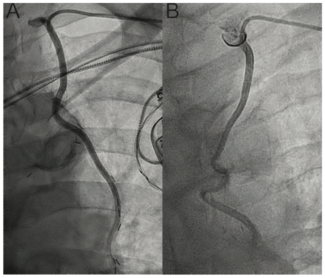

Peripheral artery disease (PAD) is common among patients undergoing transfemoral (TF) transcatheter aortic valve replacement (TAVR) and is associated with worse outcomes.1 Criteria for unfavorable TF anatomy include small-diameter vessels and...